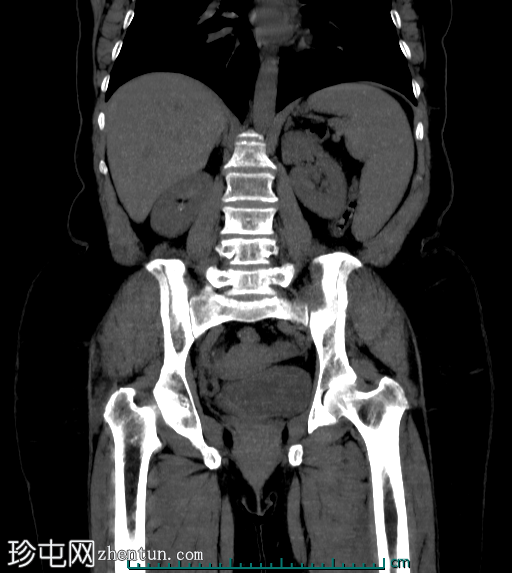

冠状位最大强度投影(MIP)

平扫

阑尾中段可见一放射性不透光阑尾粪石(冠状位和矢状位图像均可见),导致远端扩张。阑尾尖端直径达10 mm,呈充满液体的形态,周围可见脂肪条索,提示阑尾尖端炎。阑尾近端外观正常。

其他辅助发现包括:胆囊切除夹、亚厘米级肝血管平滑肌脂肪瘤、亚厘米级肝囊肿、左右肾结石。